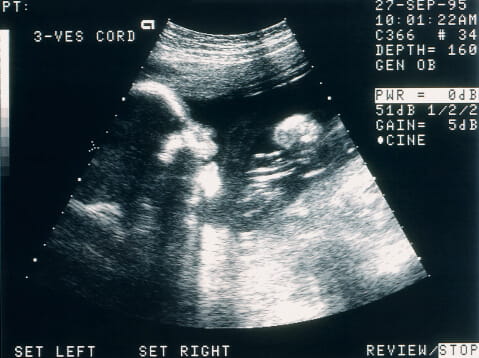

Sonograms assist doctors in evaluating organs for infections, damage, or disease. Pregnant women may get ultrasounds to generate sonograms of the fetus. Doing so allows a doctor to check a baby’s development and health.

Reading a Sonogram Picture

Reading the sonogram from a prenatal ultrasound is easy if you know what to look for. For example, black areas generally indicate fluid, such as amniotic fluid or blood. Bright white areas indicate solid structures such as bone. In between would be shades of gray that would represent organ structures. With that in mind, identifying things like the baby’s head or legs can help you get oriented.